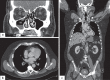

This report presents a rare case of scleritis with peripheral ulcerative keratitis secondary to granulomatosis with polyangiitis (GPA). A 65-year-old Caucasian male presented to a regional ophthalmology service with an atypical red eye. His immune work-up demonstrated positive anti-neutrophil cytoplasmic IgG autoantibodies (ANCA) with anti-proteinase 3 antibody (PR3) elevation. Multi-system vasculitis was discovered including lung, liver, bladder, prostate, nasal and paranasal sinuses involvement. His ocular sequelae included significant peripheral corneal thinning requiring cyanoacrylate gluing, juxtalimbal conjunctival resection, and bandage lens placement. He was treated with systemic methylprednisolone and rituximab achieving remission with ongoing prednisone and methotrexate maintenance therapy. This case demonstrates the importance of recognizing ocular manifestations of GPA as a first presentation of systemic vasculitis.